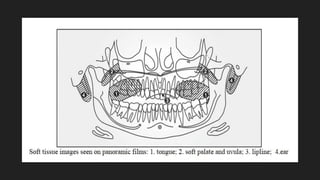

OTHER STRUCTURES

LANDMARKS WHICH APPEAR AS RADIOPAQUE:

· Tongue

· Soft palate

· Uvula

· Ear

· Lip Line

LANDMARKS WHICH APPEAR AS RADIOLUCENT:

· Palatoglossal air space

· Nasopharyngeal air space

· Glossopharyngeal air space

POINTS FOR STRUCTURES:

1. Tongue: It appears as a radiopaque area superimposed over the posterior maxillary teeth.

2. Soft palate and uvula: It is represented as radiopacity located diagonally posteriorly and

inferiorly from the maxillary tuberosity region.

3. Lipline: It is seen in the anterior teeth region. The areas of the teeth covered by lips appear

more radiopaque.

4. Ear: It is marked as a radiopaque shadow that projects anteriorly and inferiorly from the

mastoid process.

5. Palatoglossal air space: It appears as a radiolucent band located above the apices of the

maxillary teeth.

6. Nasopharyngeal air space: It is a diagonal radiolucent band located superior to the radiopaque

shadow of the soft palate and uvula.

7. Glossopharyngeal air space: It is a vertical radiolucent band superimposed over the

mandibular ramus.

8. The epiglottis can often be seen as a thin finger-like projection extending from the posterior

tongue, below the angles of the mandible